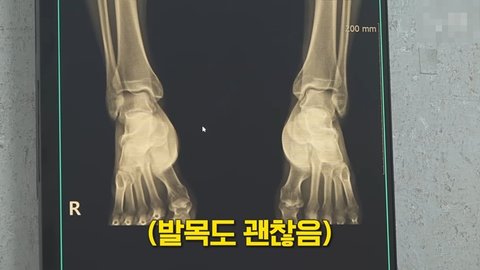

아니 션은 물론이고 많은 사람들이 걱정했던 무릎 관절도 멀쩡함

발목이랑 무릎 정도는 그렇게 뛰는데 별로 안 좋을 줄 알았다고 진짜 부러워하심ㅋㅋㅋㅋㅋㅋㅋㅋㅋㅋㅋㅋㅋㅋㅋㅋ